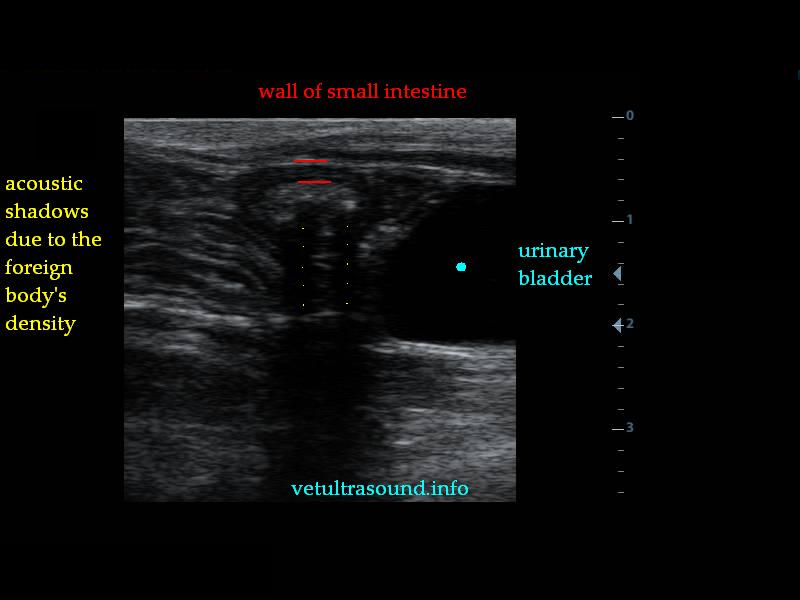

Findings: Α distention of the small intestine was noted. A corrugated small intestinal loop was found (pic1), which led to an acoustic shadow (pic2-3). This was because of an intraluminal foreign body, which was causing a partial obstruction of the small intestine.

Ευρήματα: Διάταση του πεπτικού σωλήνα με αφθονία υγρών και αέρα. Βρέθηκε τμήμα του λεπτού εντέρου με έντονη πτύχωση του βλεννογόνου του (pic1) και παρουσία πιθανού ενδοαυλικού ξένου σώματος το οποίο δημιουργούσε μερική στένωση του εντέρου και ακουστική σκιά πέραν αυτού (pic2-3).